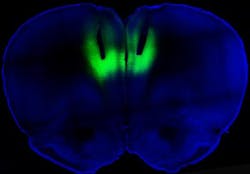

To test whether altering the activity in this brain region could impact addiction, Chen and his colleagues employed optogenetics to shut the activity on and off using a laser. First, they took light-sensitive proteins called rhodopsins and used genetic engineering to insert them into neurons in the ratâs prefrontal cortex. Activating this region with a laser tuned to the rhodopsins turned the nerve cells on and off. Turning on these cells wiped out the compulsive behavior, while switching them off turned the non-addicted ones into addicted, the researchers found.